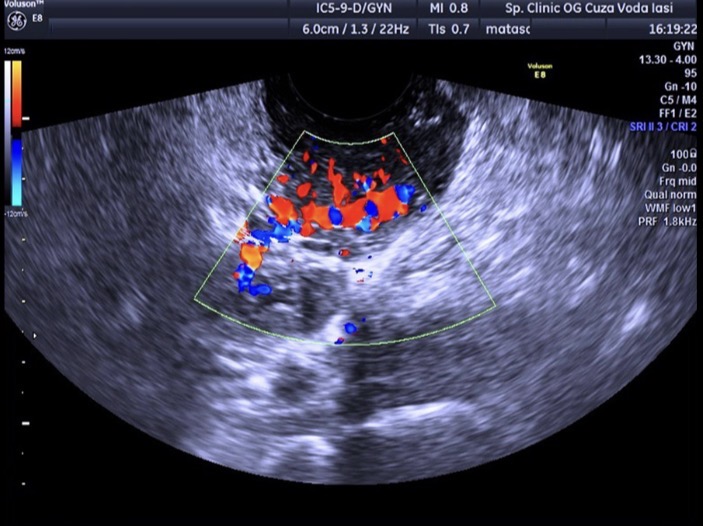

Figure 3. Трансвагинальное УЗИ: усиленный кровоток вокруг эктопической беременности с симптомом «огненного кольца», высокий пульсационный индекс.